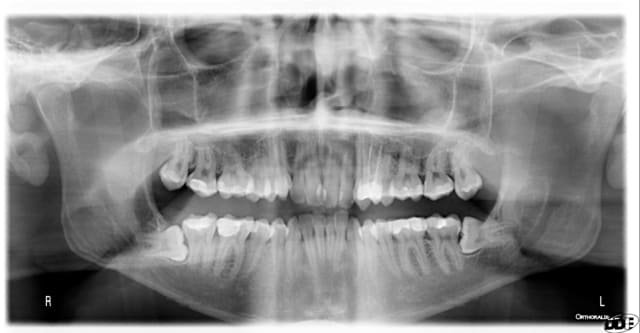

Changement en 4 ans de 17ans à 21 ans?

Ton panorex céramik est extraordinaire, j'aurais mis le titre: potentielle d'éruption dans la branche montante

Excellent exemple d'un cas où il fallait agir...

J'aurais enlever dans la 1er pano, 100%, aucune hésitation.

Dans la 2e pano, j'adresse et le pauvre patient aura des emmerdes.

Dans la 1er pano, j'enlève toutes les 8

Dans la 2e pano, je touche pas.

Note: il y a une obturation sur la 18 ????????

la 18 et 28 sont en occlusion avec le tiers distal des 37-47..

Pas grave, ça pousse la bouffe au distal des 37 et 47, et tu as là des 48 et 38 bien mal placées.

Enlève déjà les 18 et 28.

Vu le niveau d'hygiène du patient quand on compare le nombre d'obturations entre 17 et 21 ans, la malposition...on peut probablement prédire une complication ifectieuse sur 38-48 dans les années

Concernant les 18-28 sont simples à enlever, en une séance et le tour est joué.

Concernant les 38-48 il n'y a en principe pas de difficulté opératoire mais à présent il ne faudra les enlever que si y'a des symptômes infectieux récurrents.

pas d'accord pour la 38 communication en bouche indication formelle d'extraire, ne pas attende infection à 50 ans et perdre la 37 du même coup.

Et la 48, ne pas attendre non plus, car ça sera la même chose.

Illico, exo des 4 dds.

38 et 48 à extraire ou alors tu vas jouer à la roulette russe pour le maintien des 7.

Demande un dentascan pour la 48 pour programmer une éventuelle coronectomie.